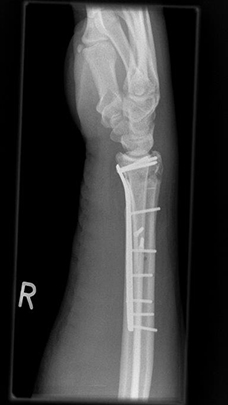

Komplexe rechtsseitige Unterarm-Handgelenksfraktur nach Osteosynthese

Komplexe rechtsseitige Unterarm-Handgelenksfraktur nach Osteosynthese, frontal